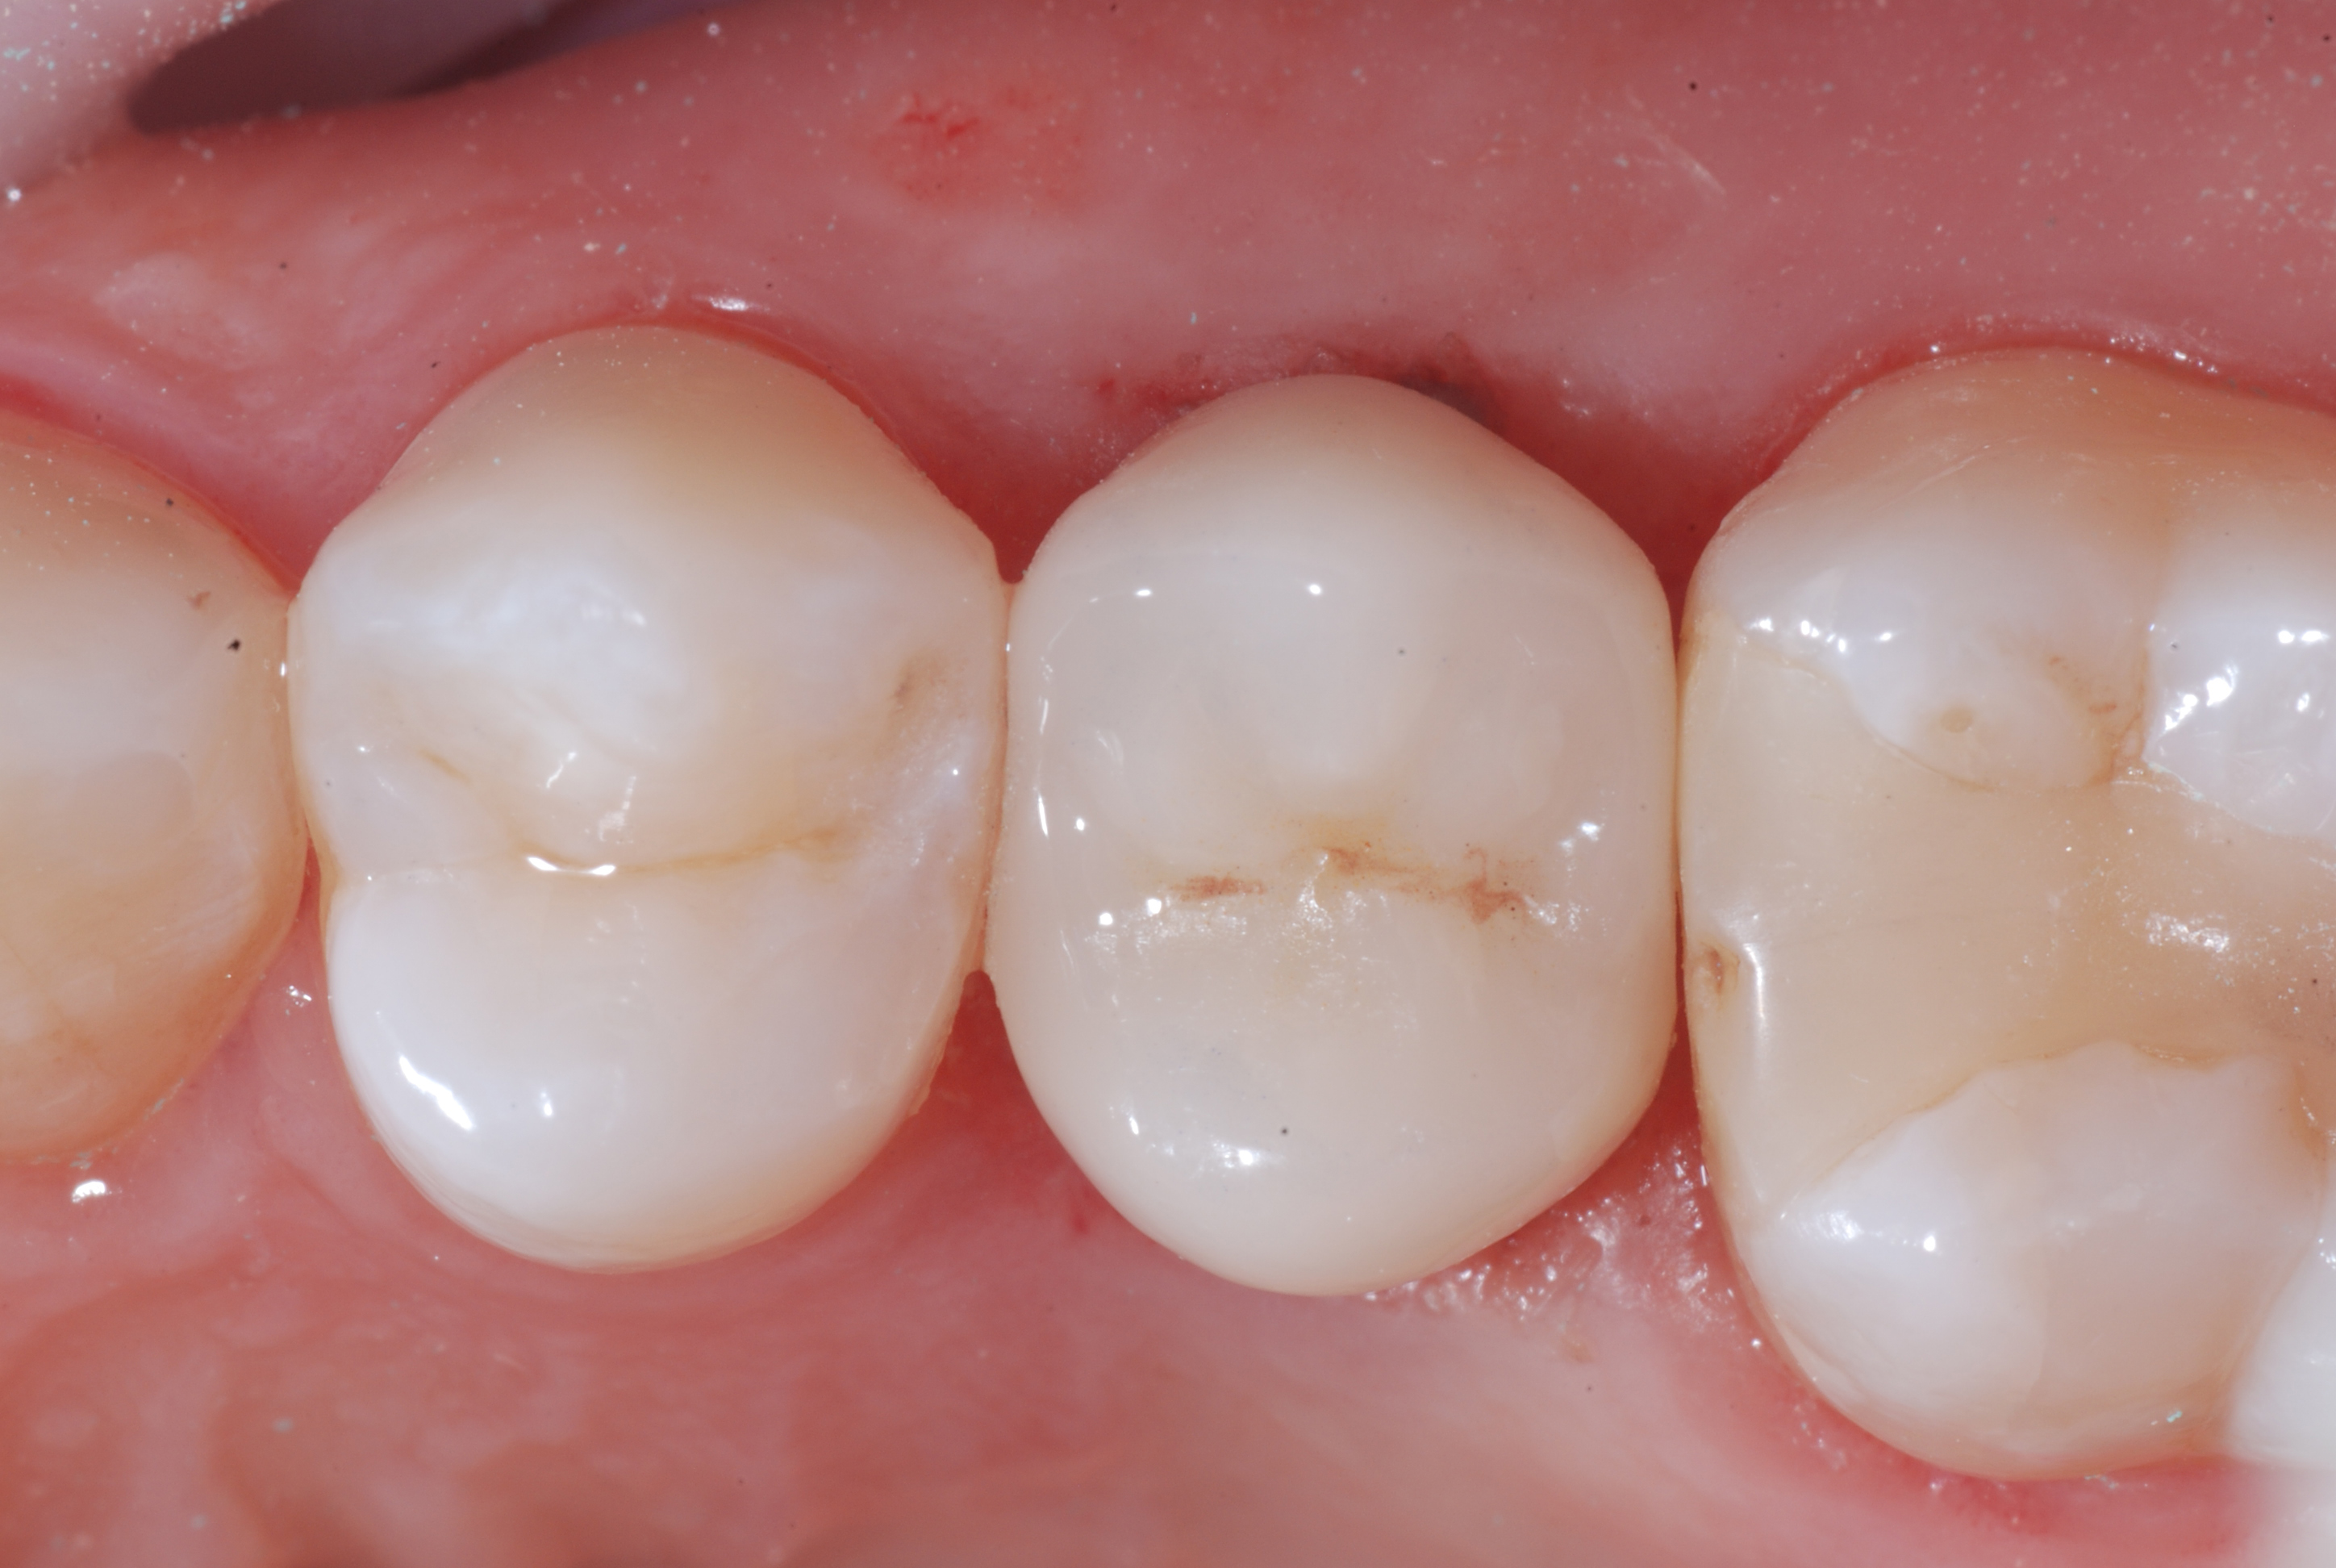

Figure 11. The crown on tooth 25 after polishing with the three eZr Garrison rubber points.Figure 12. Apical X-ray of the surgically extruded tooth 25 at the end of the restoration.

Figure 13. Clinical image of the same tooth at a follow-up visit.